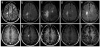

Progressive multifocal leukoencephalopathy is caused by the JC polyomavirus (JCV) and is one of the most feared complications of HIV-1 infection. Unlike other opportunistic infections, this disease can present when CD4 counts are higher than those associated with AIDS and when patients are receiving combined antiretroviral therapy, either shortly after starting or, more rarely, during long term successful treatment. Clinical suspicion of the disease is typically when MRI shows focal neurological deficits and associated demyelinating lesions; however, the identification of JCV in cerebrospinal fluid or brain tissue is needed for a definitive diagnosis. Although no specific treatment exists, the reversal of immunosuppression by combined antiretroviral therapy leads to clinical and MRI stabilisation in 50-60% of patients with the disease, and JCV clearance from cerebrospinal fluid. A substantial proportion of patients treated with combined antiretroviral therapy develop inflammatory lesions, which can be associated with either a favourable outcome or clinical worsening. The reasons for variability in the natural history of progressive multifocal leukoencephalopathy and treatment responses are largely undefined, and more specific and rational approaches to management are needed.